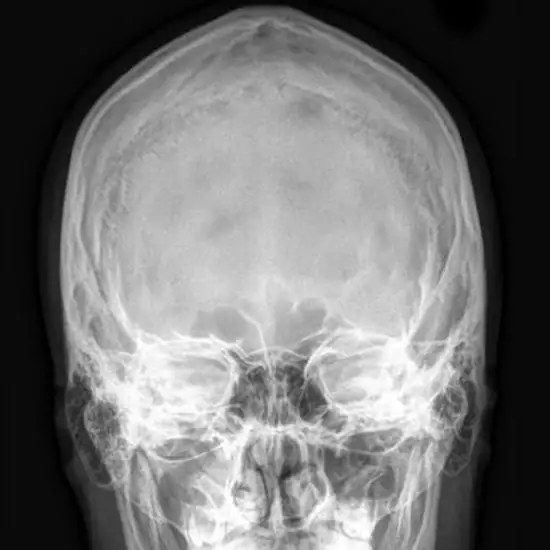

X-ray Mandible AP/Lateral

An X-ray of the mandible (jaw) is a painless and safe procedure that uses a small amount of radiation to see the structures of the jaw bone, the temporomandibular joint (TM joint), and the surrounding soft tissues.